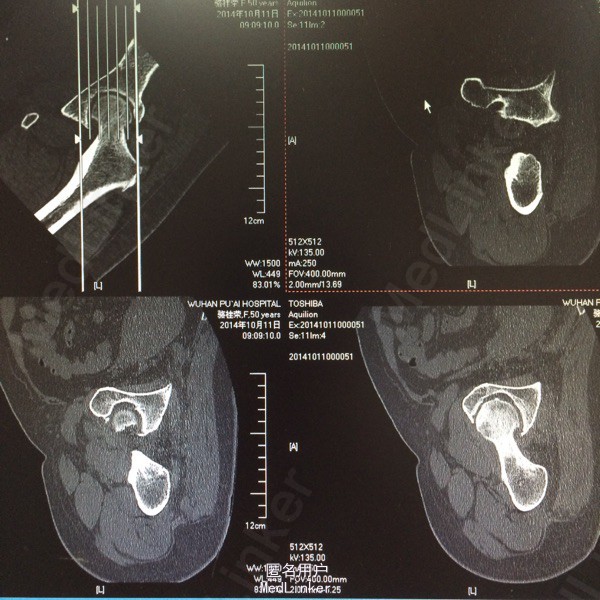

患者,女,50岁。因“双髋关节疼痛活动受限一年余”入院。 患者一年余前无明显诱因感双髋关节疼痛,活动后症状加重,休息后稍有缓解,不伴发热、咳嗽,否认明确外伤史。于今年8月在我院门诊拍片(M00085020)示:双侧股骨缺血性坏死。今为求进一步治疗来我院求诊,门诊查体阅片后以“双侧股骨头缺血性坏死”收住我科。 自起病以来,患者饮食睡眠可,二便正常,体力下降,体重无明显改变。 既往:否认肝肾病史,否认食物、药物过敏史

体格检查:T 36.8℃ P 78次/分 R 20 次/分 BP 142/96mmHg,神志清醒,平静面容,扶拐跛行步入病房,查体合作。发育正常,全身皮肤未见黄染,浅表淋巴结未及肿大,头颅无畸形,双侧瞳孔等大等圆,光反射灵敏。颈软,胸廓无畸形,双肺呼吸音清晰,未闻及干湿性啰音。心律齐,各瓣膜听诊区无杂音。腹平软,无压痛反跳痛,脊柱无畸形,各棘突无压痛。双上肢正常。 专科情况:双髋关节未见明显肿胀,腹股沟中点处深压痛,下肢无轴向叩击痛,双髋关节活动度因疼痛减小,4字征阳性,双足背动脉搏动可及,各趾感觉、活动正常,直腿抬高试验阴性,双下肢无明显短缩。 门诊资料:我院MRI(M00085020)示:“双侧股骨头缺血性坏死”。

初步诊断:双侧股骨头缺血性坏死 鉴别诊断:X线片上未见骨肿瘤,骨囊肿等征象可与肿瘤相相鉴别,具体有待于进一步检查。 诊疗计划:1.卧床休息,暂不负重,对症支持处理。 2.完善相关检查(血、尿分析、肝肾功能、骨盆平片、髋关节CT、胸片ECG、心脏彩超等)。 3.择期手术治疗(髋关节置换术)。